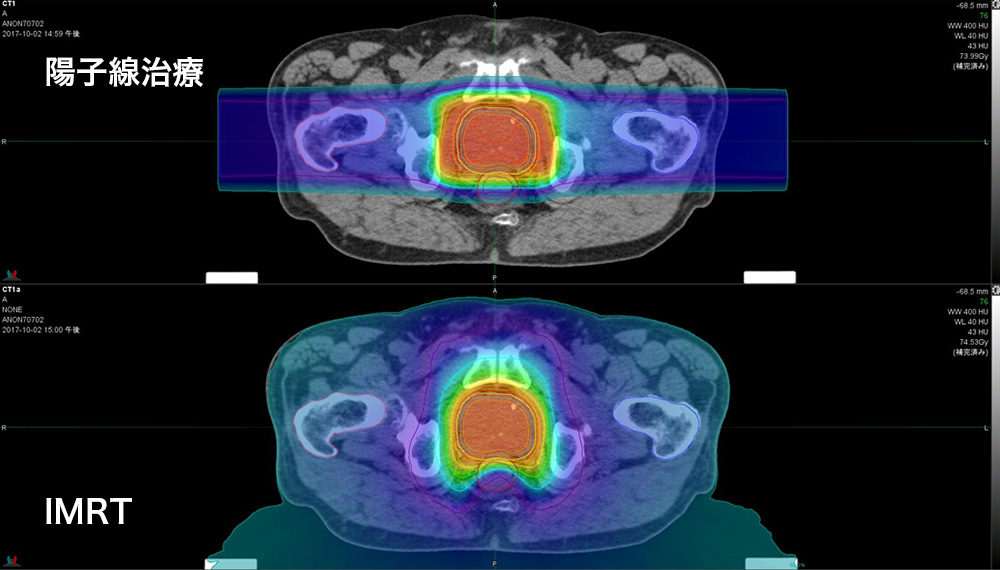

陽子線治療は、亜原子粒子の一種である陽子を使用します。 X 線とは異なり、陽子線治療は周囲の組織へのダメージが少なくなります。これにより、治療の副作用や周囲の臓器への損傷を軽減できます。

治療中、医師または技師は装置を使用して放射線を集中させ、がんの部位に照射します。人は自宅ではなく、病院または治療センターで治療を受けます。従来の放射線とは異なり、陽子線治療はほぼすべての放射線をがん部位に照射し、近くの組織を保護します。

陽子線治療はまた、近くの臓器への放射線を軽減し、損傷やその後の癌のリスクを軽減する可能性があります。